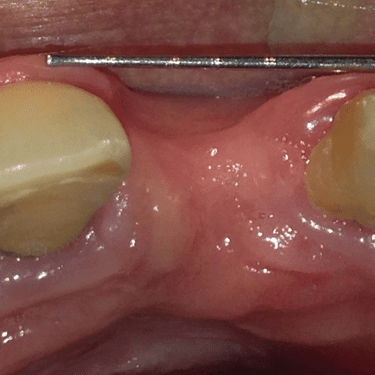

Pérdida de un diente único

La pérdida de un diente único es cuando un solo diente se ha caído o ha sido extraído, y se necesita un implante para reemplazarlo.

Los pacientes pueden notar un espacio donde solía estar el diente. Esta condición puede afectar la estética y la función masticatoria.

El tratamiento incluye la colocación de un implante dental para restaurar el diente perdido.